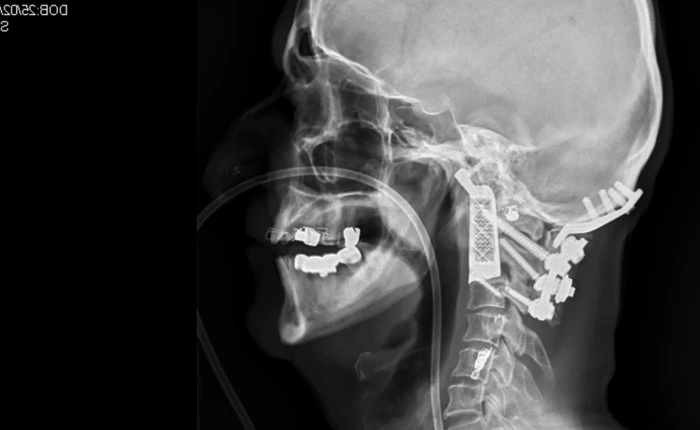

Bệnh nhân này đã vô tình mắc căn bệnh ung thư sụn ác tính, cực kì hiếm gặp.

-

Bệnh nhân đang dần dần hồi phục.